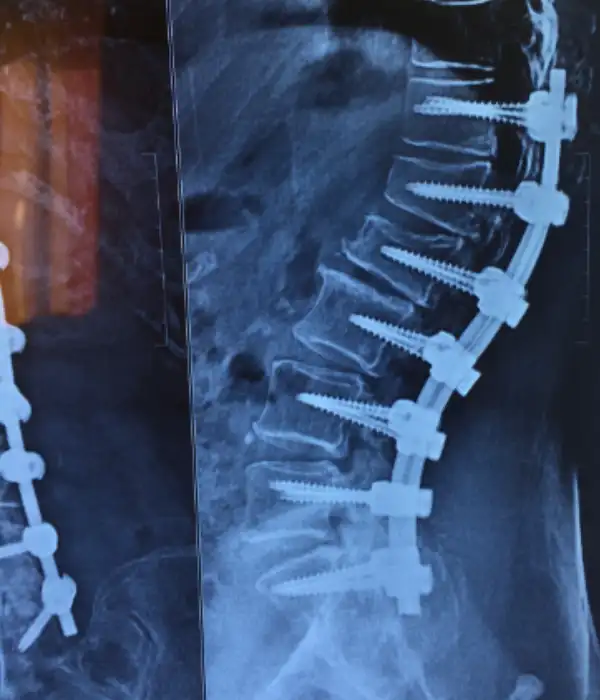

Degen Scoliosis

Degen Scoliosis Post operative Xray

- Degenerative Adult Scoliosis

- Kyphosis